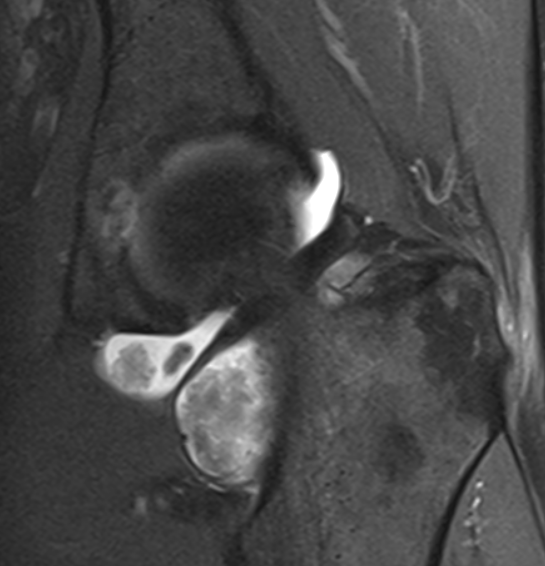

Pigmented Villonodular Synovitis